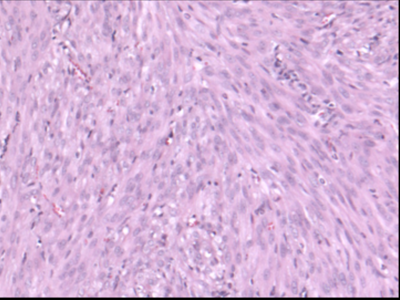

Histologic image of leiomyosarcoma

How can we better diagnose and treat leiomyosarcoma?

Leiomyosarcoma is a poorly understood sarcoma that arises from smooth muscle cells or their progenitors. Leiomyosarcoma presents diagnostic and therapeutic dilemmas, with multiple molecular subtypes and few common mutations or therapeutic targets between patients.